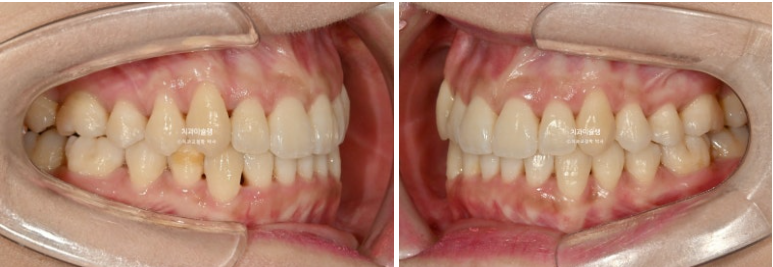

23.08~25.10

중심선의 개선, 과개교합의 개선, 덧니의 개선, 블랙트라이앵글의 개선이 보입니다.

앞니는 뒤로 들어가지도, 나오지도 않고 잘 유지되었습니다.